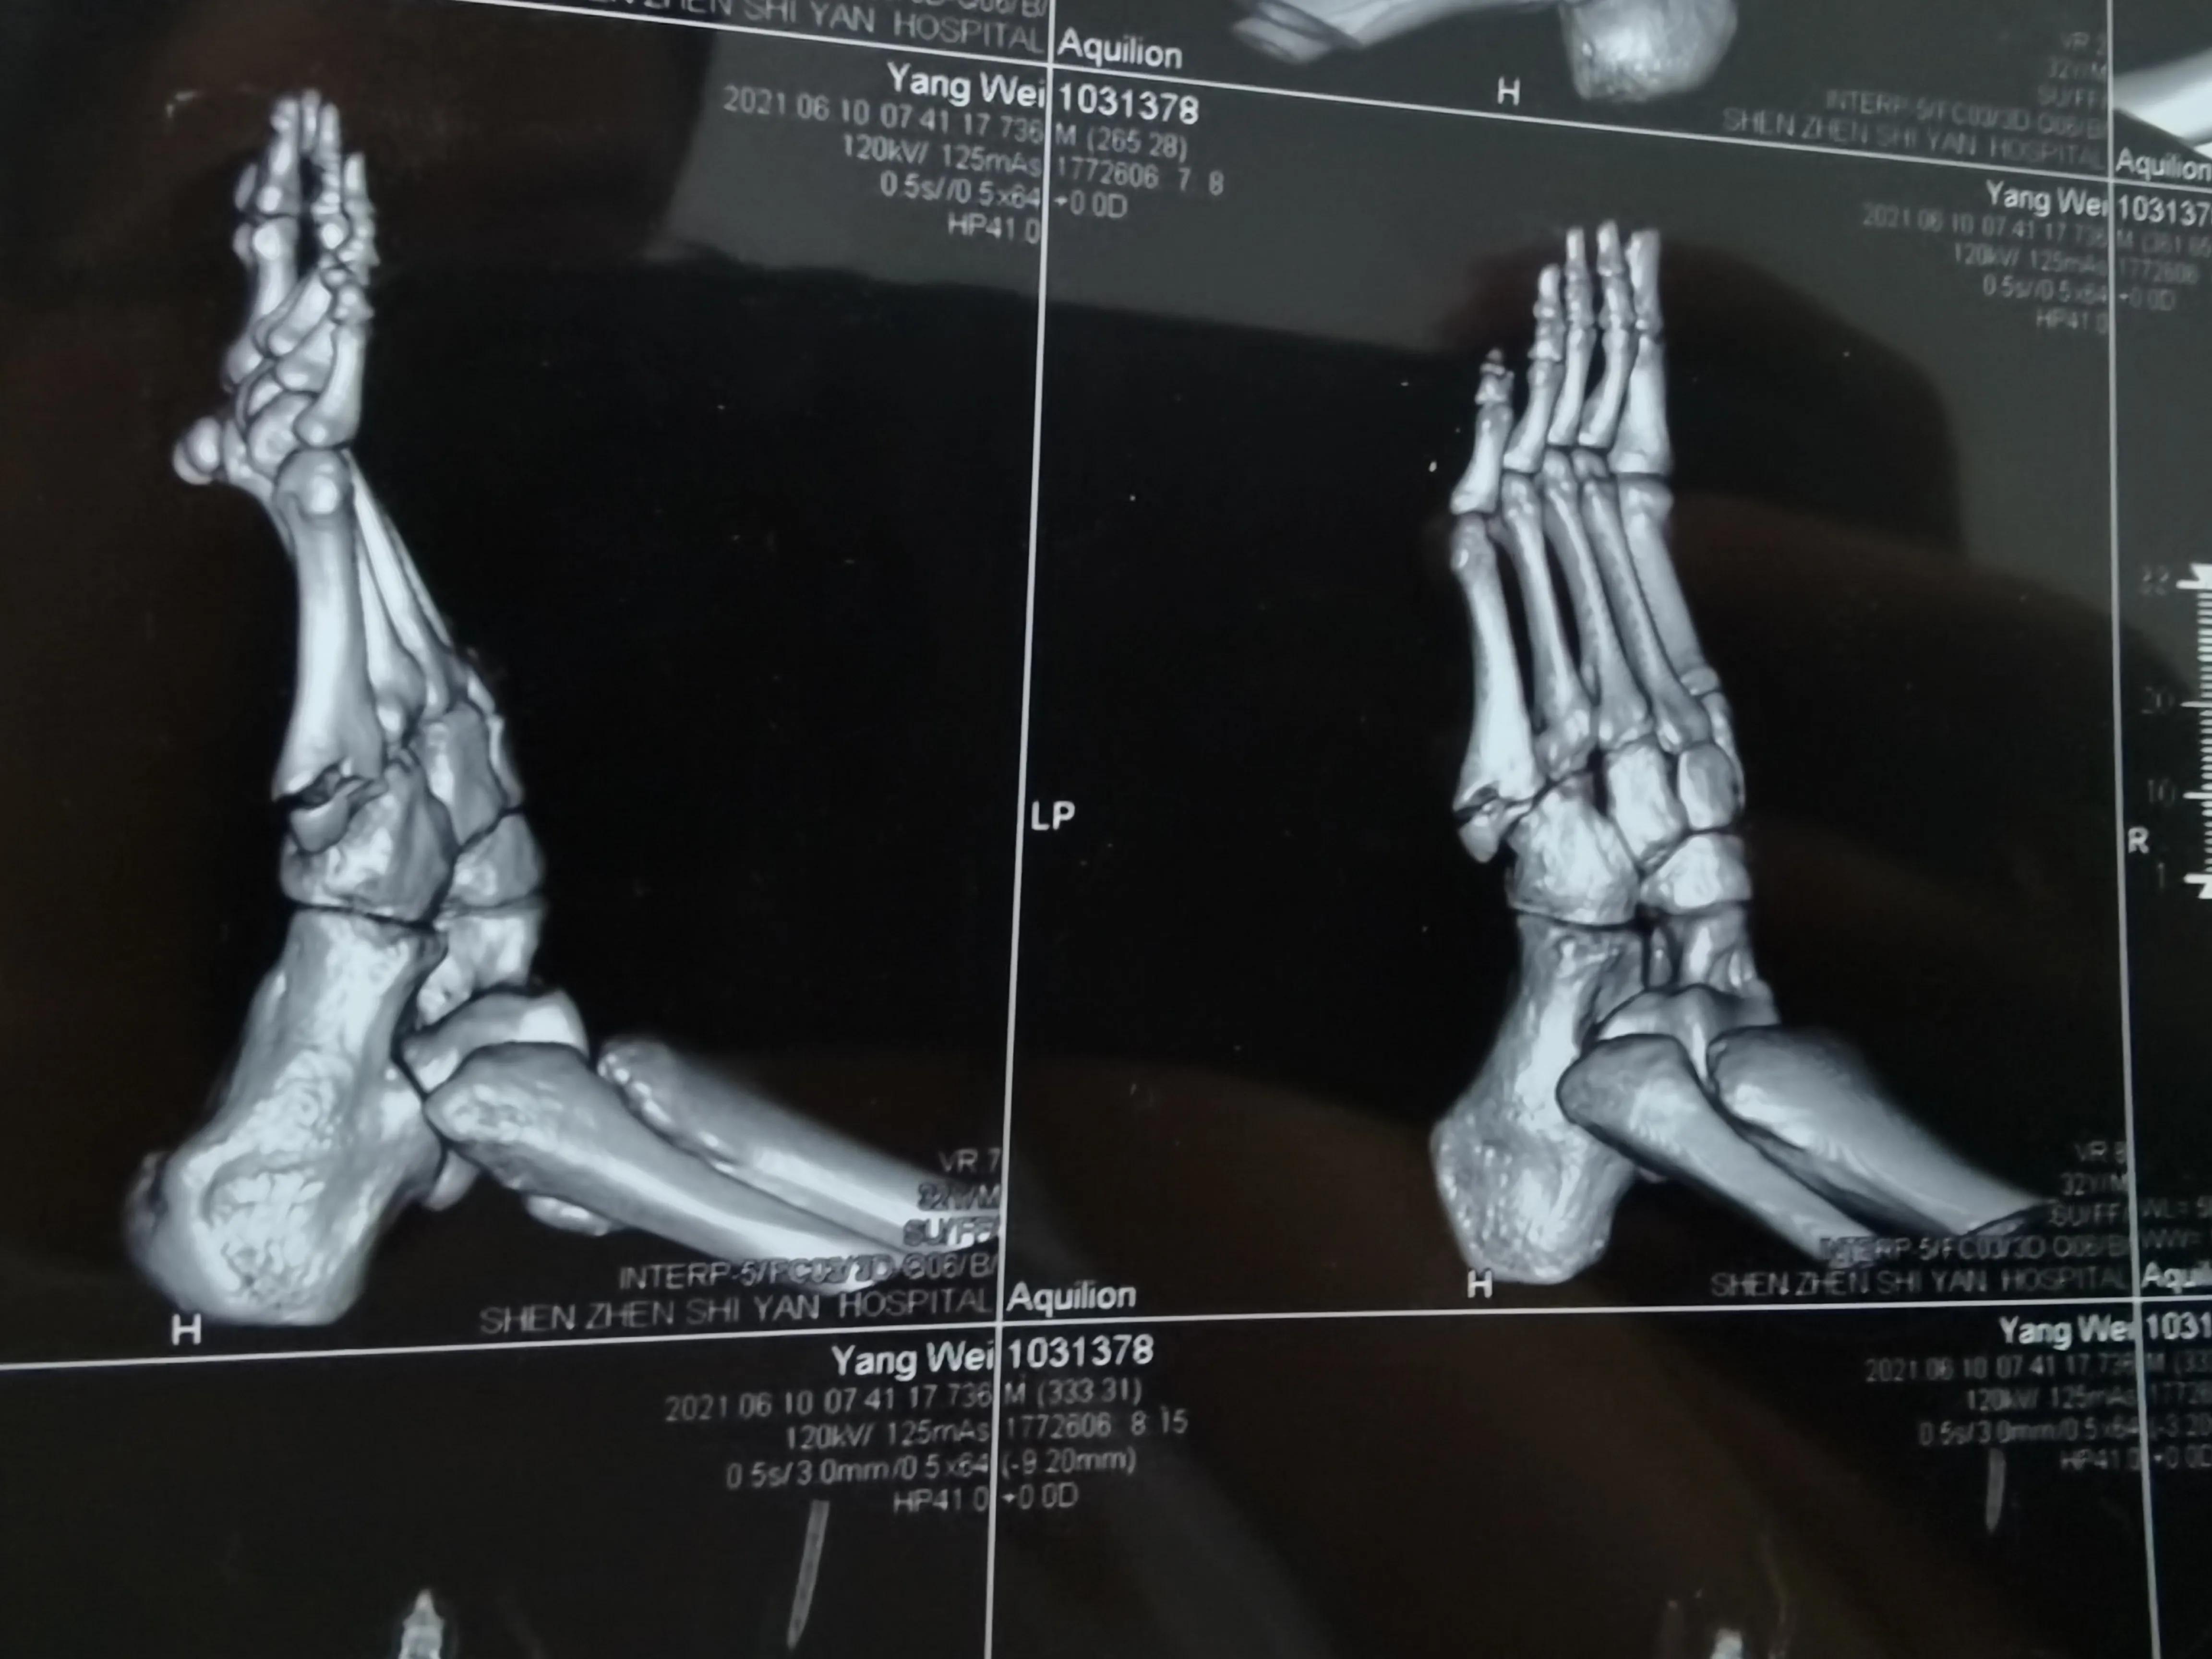

这是CT诊断书

看片子骨缝比较大了,有点移位,而且中间崩碎了一块,一直找不到,后来复查才发现那个碎片掉落在骨缝当中了

此图可以看见中间碎片在骨缝里面

6月底复查,骨缝小的地方已经有了一点愈合的痕迹,医生说如果手术可以在红线位置打个钉子,但是现在打会破坏内部已经开始愈合的部分,建议继续保守……